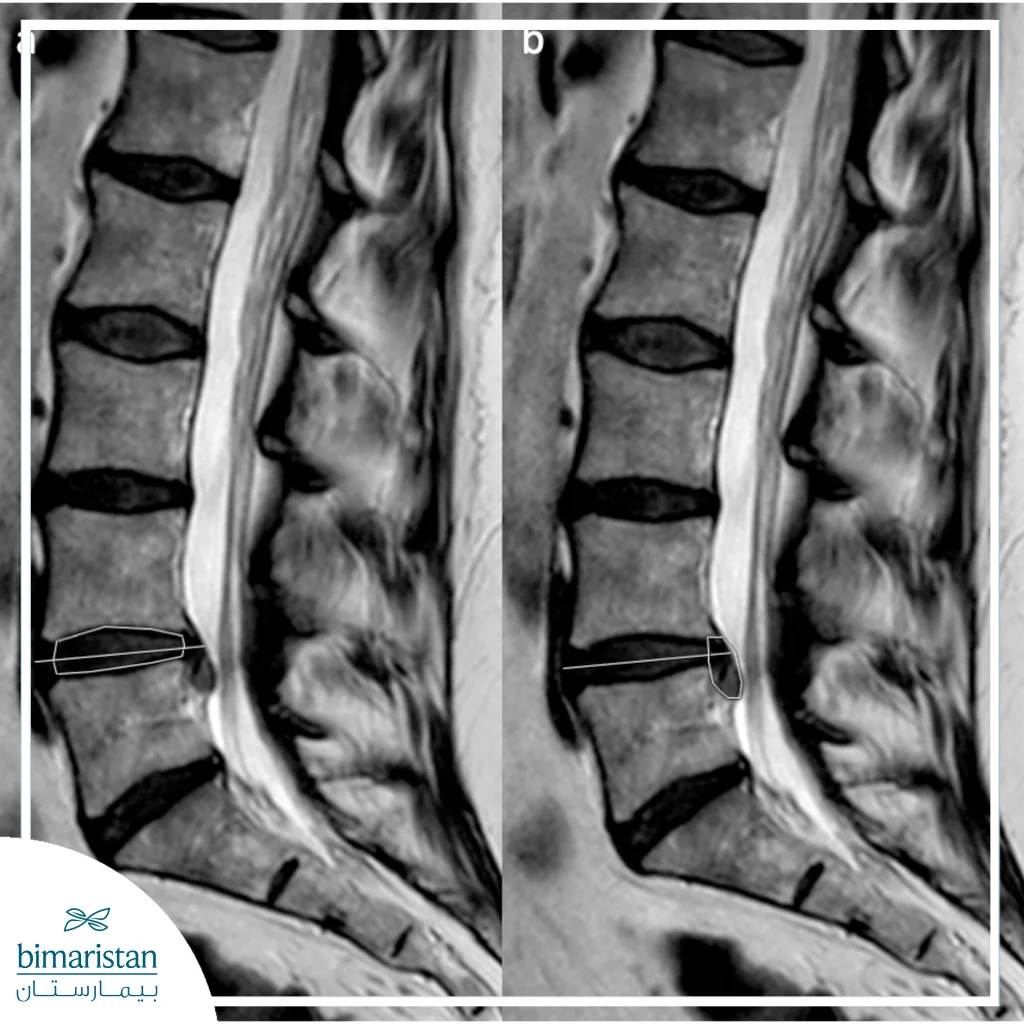

The patient undergoes blood tests and a modern MRI to determine the exact location and degree of the slippage, then the surgeon explains the steps and details of the operation to the patient, and the patient is given an expected date of recovery and return to normal life.